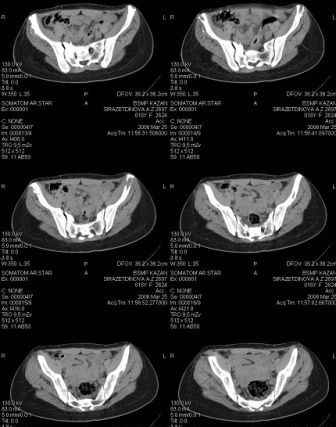

Предоставляю срезы. Если пациентку функционально ничего не беспокоит, стоит ли навязывать ей лечение.

Если пациентка не собирается жить половой жизнью и вообще собирается в моностырь, то пожалуй, я бы согласился с Вами и навязывать лечение не стал.

Но если девочка более активна в жизни, я бы рекомендовал ликвидировать укорочение и вернуть тазу естественную форму.